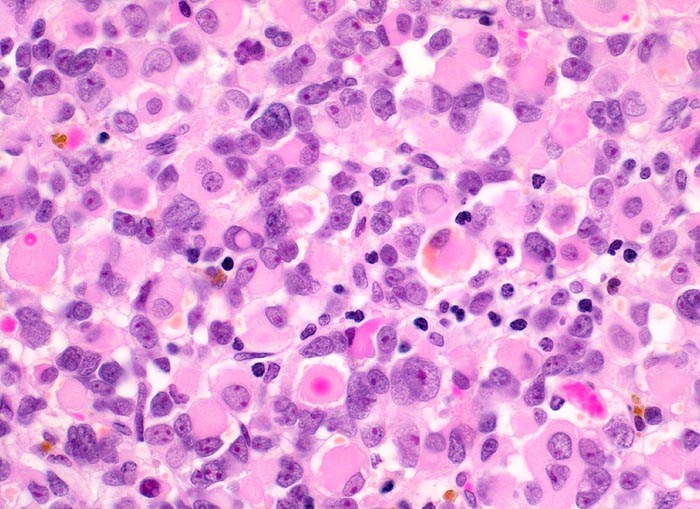

embryonales Rhabdomyosarkom

Dieser Tumor besteht überwiegend aus Rhabdomyoblasten mit reichlich eosinophilem Zytoplasma und exzentrisch gelagerten grossen dunklen Kernen mit eosinophilen Nukleolen. Daneben sind einzelne primitive Zellen mit wenig Zytoplasma und Entzündungszellen erkennbar sowie gelbbraune Hämosiderinablagerungen. Eine Querstreifung ist nich nachweisbar.

Schmerzloser rasch wachsender Tumor im oberen inneren Quadranten der Orbita mit Verdrängung des Bulbus nach temporal. Diplopie.

Histologie

Vergrösserung

400